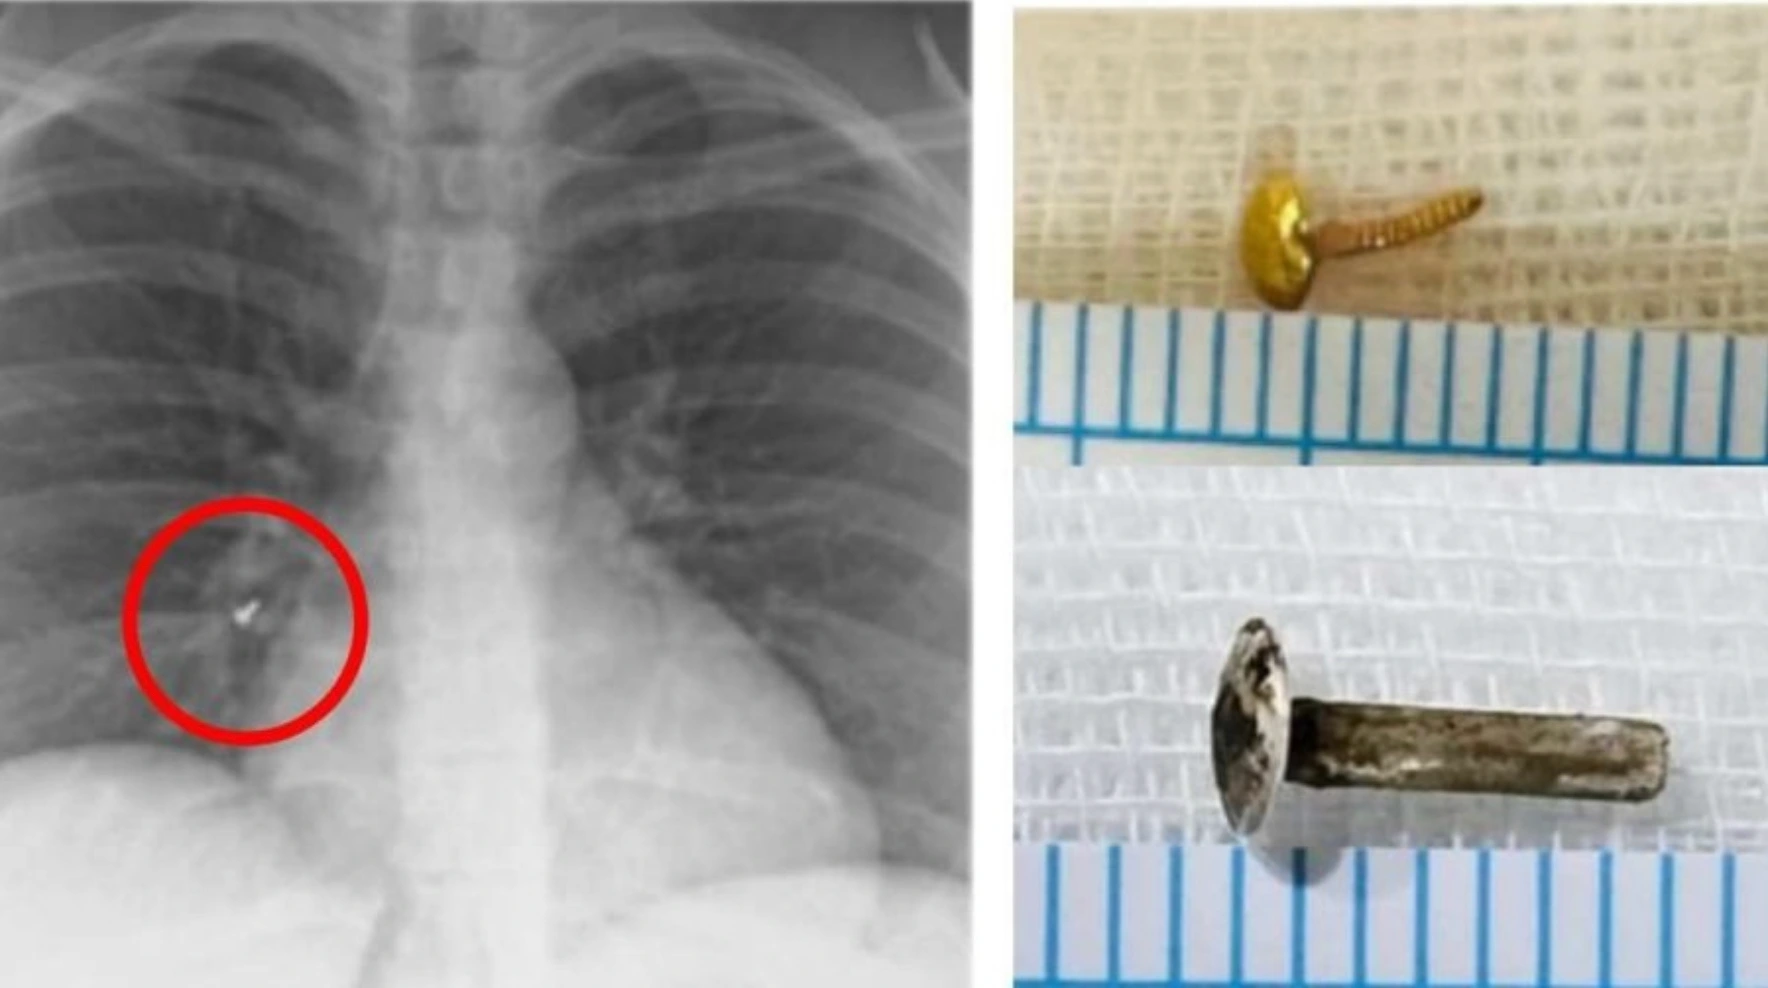

ശ്രദ്ധിച്ചില്ലെങ്കിൽ അത് വലിയ അപകടത്തിന് കാരണമാകുമെന്നാണ് ഡോക്ടർമാർ മുന്നറിയിപ്പു നൽകുന്നത്. രണ്ടാഴ്ചക്കിടെ മൂന്ന് സ്ത്രീകളുടെ ശ്വാസകോശത്തിൽ നിന്നാണ് അമൃത ആശുപത്രിയിലെ ഇൻ്റർവെൻഷൻ പൾമനോളജി വിഭാഗം മൂക്കുത്തിയുടെ ആണി നീക്കം ചെയ്തത്. വിദേശയാത്രയ്ക്കുള്ള വിസ നടപടികളുടെ ഭാഗമായി നടത്തിയ പരിശോധനയിലാണ് രണ്ട് യുവതികളുടെ ശ്വാസകോശത്തിൽ മൂക്കുത്തിയുടെ ആണിയുള്ളത് കണ്ടെത്തിയത്. ആരോഗ്യപരിശോധനയുടെ ഭാഗമായി എക്സ്റേ എടുത്തപ്പോൾ 52 കാരിയായ മറ്റൊരു സ്ത്രീയുടെ ശ്വാസകോശത്തിലും ആണി കണ്ടെത്തി. ഇതിൽ ഒരു യുവതിയുടെ മൂക്കുത്തിയുടെ ആണ് രണ്ട് വർഷം മുമ്പാണ് കാണാതായത്. അന്ന് നിലത്ത് വീണ് നഷ്ടപ്പെട്ടിട്ടുണ്ടാകുമെന്നാണ് കരുതിയത്. എക്സറേ പരിശോധനയിലാണ് മൂക്കുത്തി കണ്ടെത്തിയത്. ആണി ശ്വാസകോശത്തിൻ്റെ വലതുഭാഗത്ത് അടിവശത്തായി തറച്ചുകിടക്കുകയായിരുന്നു. ആണി ശ്വാസകോശത്തിൽ അകപ്പെട്ടതിന് ശേഷം ഇവർക്ക് ചെറിയ തോതിലുള്ള ചുമയല്ലാതെ മറ്റ് ആരോഗ്യപ്രശ്നങ്ങളൊന്നും ഉണ്ടായിരുന്നില്ലെന്നാണ് വിവരം. ഉറക്കത്തിൽ നാം അറിയാതെ മൂക്കുത്തിയും ആണിയും മറ്റ് ഭാഗങ്ങളും ശ്വാസകോശത്തിലെത്താൻ സാദ്ധ്യതയുണ്ടെന്ന് വിദഗ്ധർ പറയുന്നു

രണ്ട് വർഷം മുൻപ് കാണാതായ മൂക്കുത്തിയുടെ ആണി ശ്വാസകോശത്തിൽ; രണ്ടാഴ്ചക്കിടെ മൂന്ന് സ്ത്രീകളുടെ ശ്വാസകോശത്തിൽ ആണികൾ കണ്ടെടുത്തു